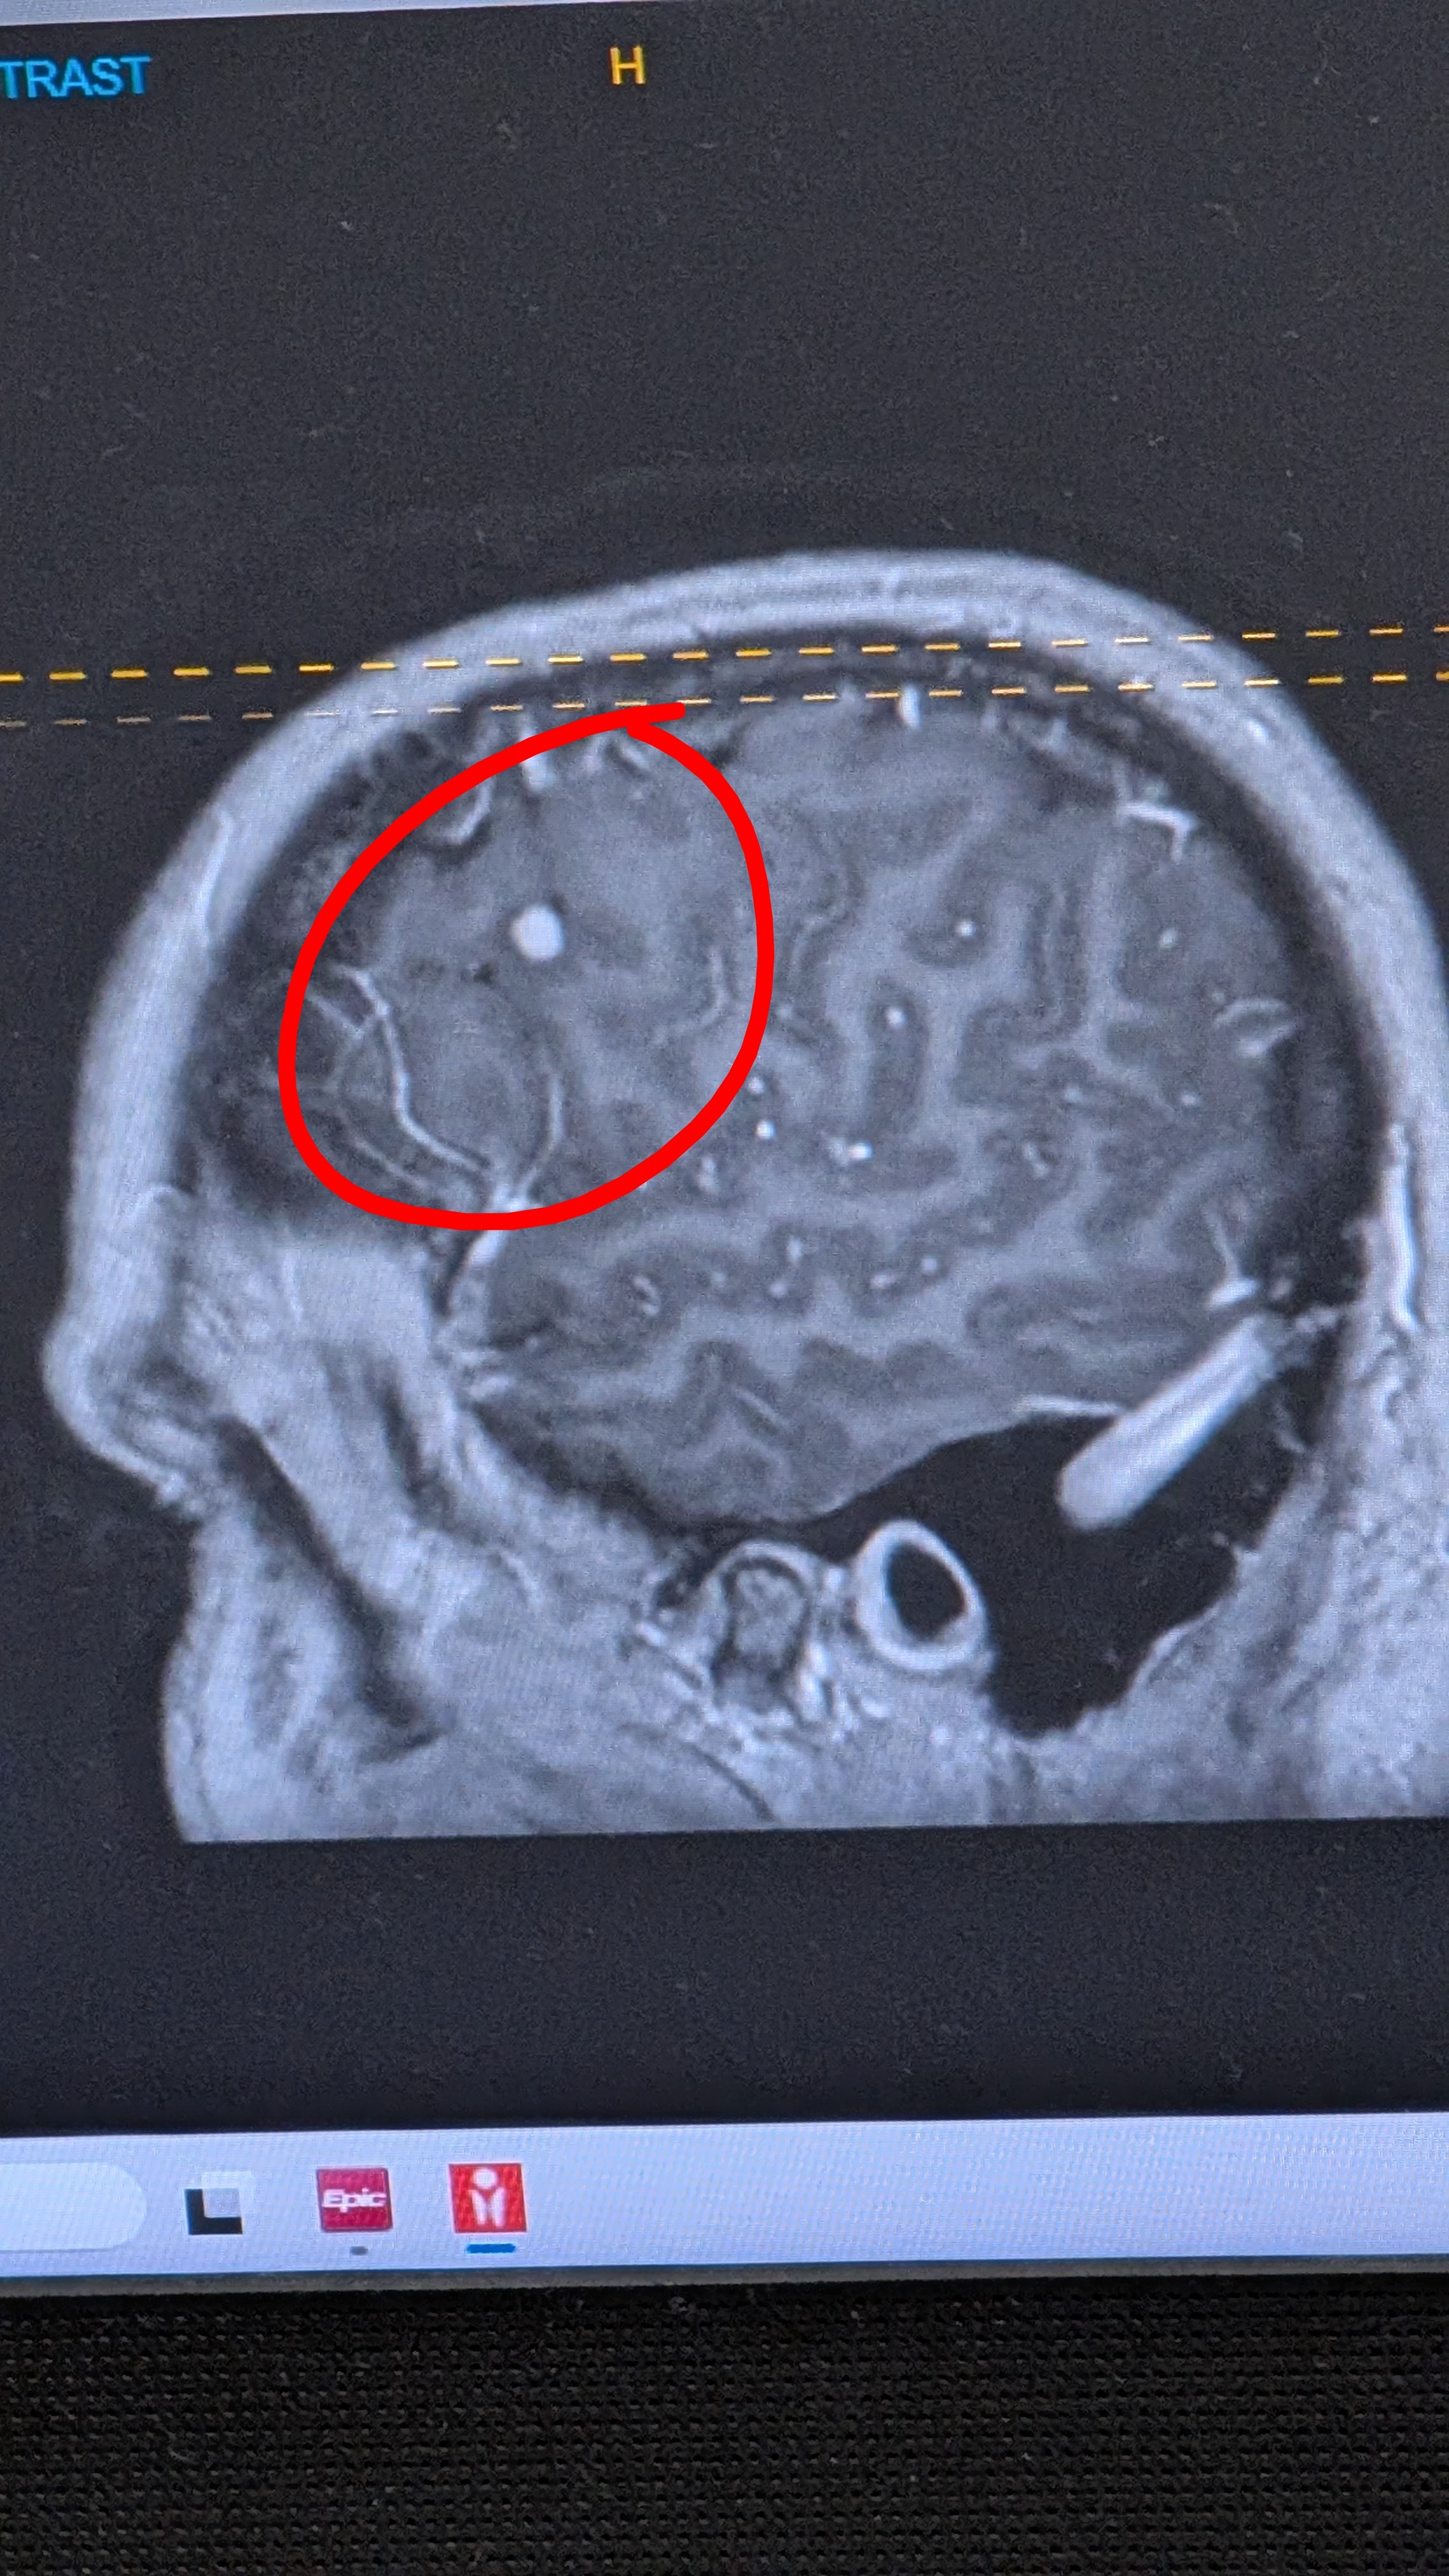

Hello all! I've created this GoFundMe to assist my sister, Becca, with the long road she has ahead. On February 19th, she had an episode when she was trying to undo her seatbelt. She got her left hand over the button but lost the ability to continue the task. Her brain was telling her hand to release the seatbelt, but it wasn't moving. She went to work the whole next week, seemingly fine. Then on February 28th, when she and my mom were home, she experienced a similar episode while she was holding a glass. This time she figured she'd better head to the ER to see what was going on. They found a 3.6 cm tumor (which is large for the brain) on her brain that was surrounded by tons of swelling. She also has 3 smaller tumors in there as well. They did some further imaging to see if there were any other areas of concern in her body. They found 6-7 lesions on her lungs, one on her adrenal gland, and one on her ovary. All of the healthcare professionals on her team were completely shocked that she wasn't a lot more symptomatic given the size of the large tumor. What we know so far is, being it's in multiple organs, it's a metastatic cancer and stage 4. We are awaiting final pathology to find out where it started and confirm if it is melanoma, or some other type, as she has had melanoma removed from her skin in the past and her surgeon described the large tumor as "very bloody," which is consistent with melanoma. Less than 24 hours after finding the mass in her brain, she went in for surgery to have it removed. Talk about a surprise! They were able to get most of it. Again, her neurosurgeon expected her to come out of surgery with mobility issues on her left side, or at the very least, numbness. She had none of that. We are so grateful that God provided her surgeon with steady hands! Before all of this, excluding the few episodes of ataxia, she thought she was perfectly fine! While this all sounds scary, cancer treatments have come a very, very long way. And we are thankful for the ability to be able to research other avenues to keep her body strong through traditional treatment. She is in good spirits and so is everyone surrounding her. She is one of the most stubborn people I have ever met! She has been training her whole life to kick this cancer's ass! She has reached her marathon and she will come out victorious! If you reach out to her, she will only accept positive prayers, vibes, and words. She is forevermore living in a positive, uplifting state of mind. No pity, no worry, no negativity allowed! ♀️